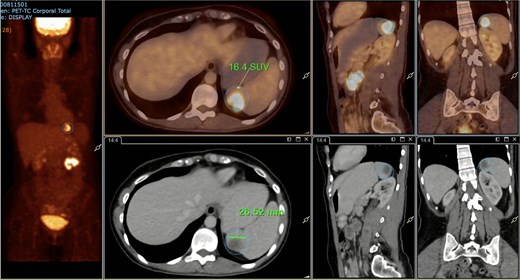

A subsequent PET/CT, performed prior to any surgical intervention, demonstrated intense radiotracer uptake in the thickened jejunal wall (SUV 17.8), in hypermetabolic mesenteric lymph nodes adjacent to the lesion (SUV 15.7), and in a 26.5-mm hypermetabolic nodule in the upper pole of the spleen (SUV 16.4) (Figs 2–4). Given these findings, lymphoma was included in the preoperative differential diagnosis.

PET/CT showing a hypermetabolic splenic nodule in the upper pole (SUVmax 16.4).